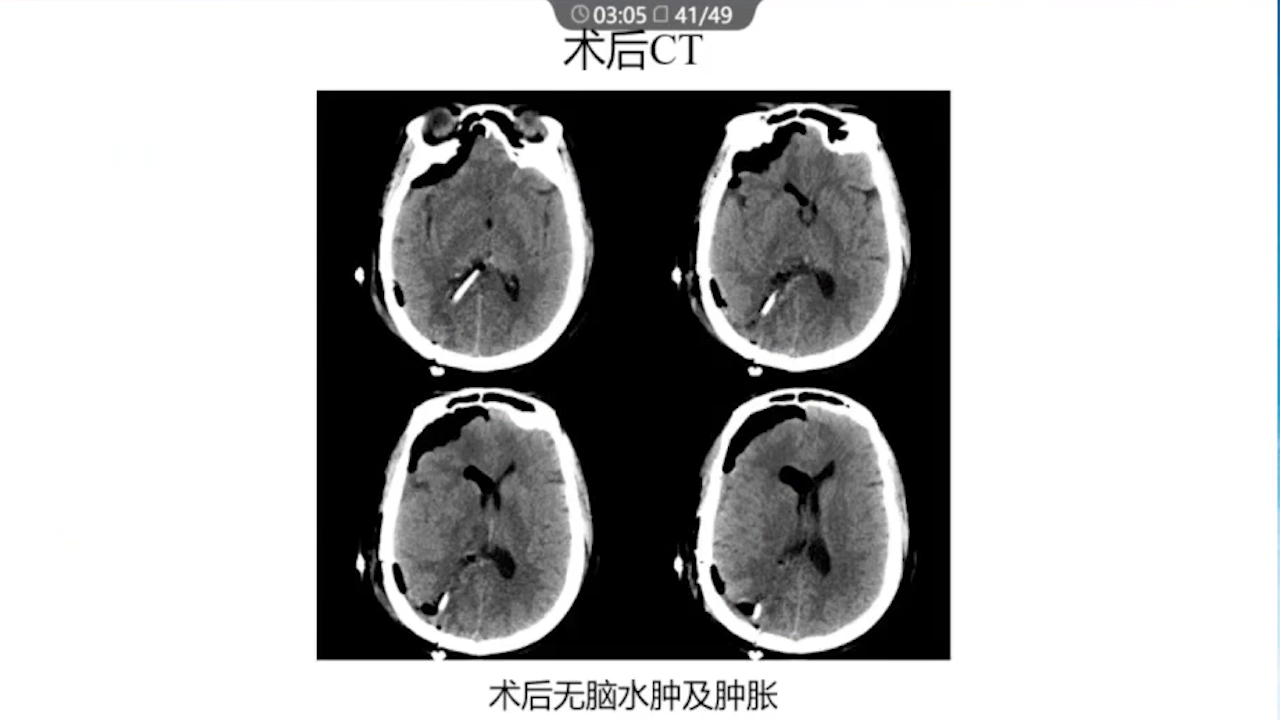

8、术后积极进行脱水治疗:如果术后脱水不及时,将可能发生严重的脑水肿,导致功能区脑组织受压、静脉回流障碍等一系列的严重反应。